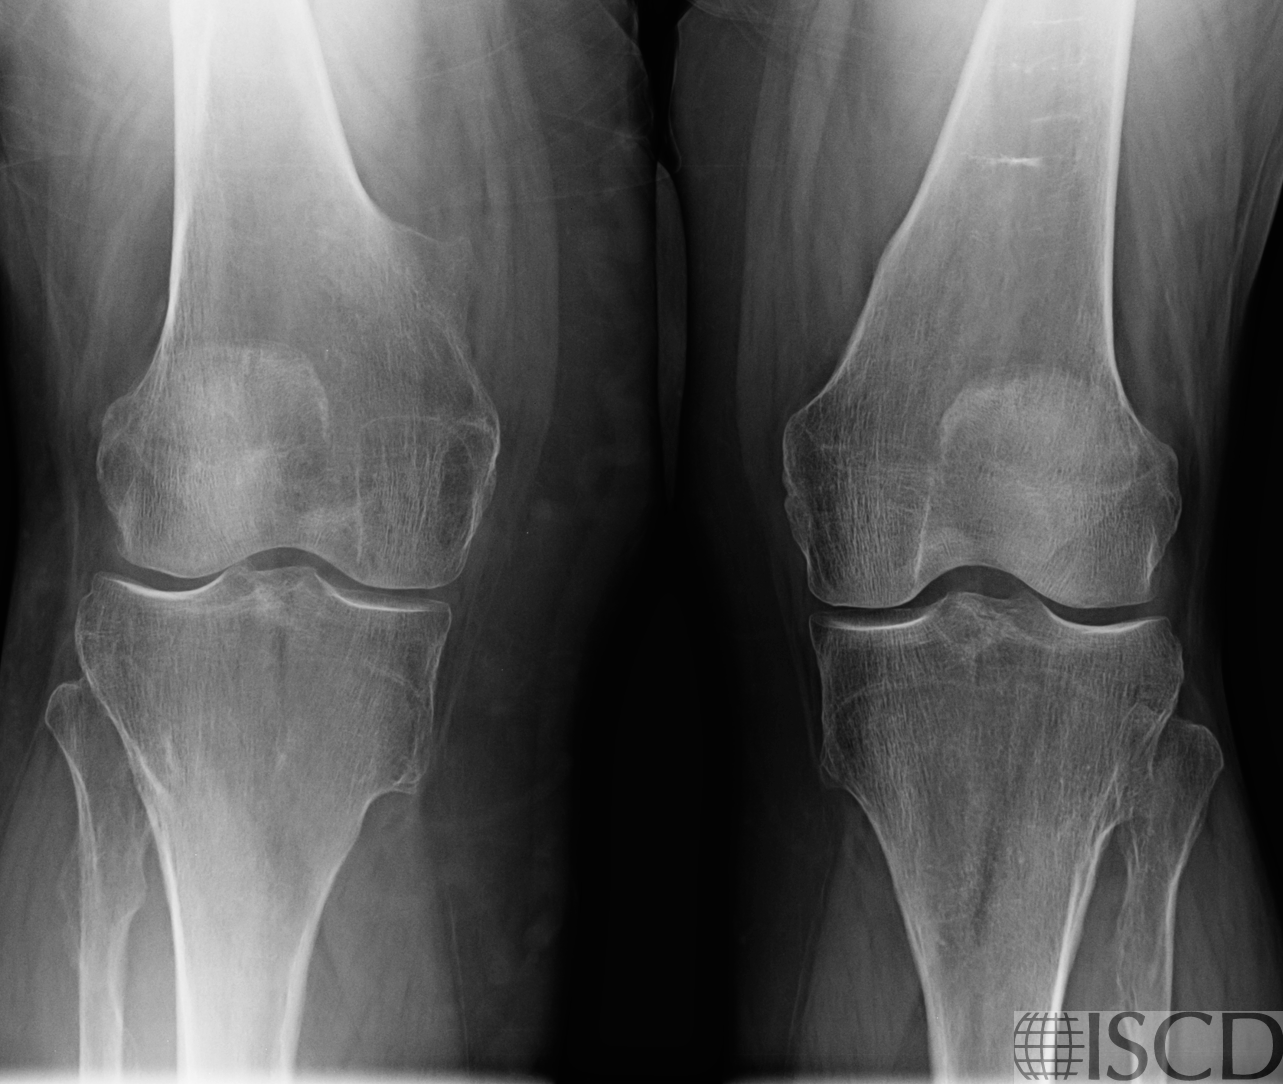

Figure 2A: X-ray knees shows multiple bony exostoses.

Left hip DXA image shows bony protrusion from the lateral cortical subtrochanteric femur. Periosteal stress reaction from an atypical femur fracture (AFF) might be considered, but the patient had received no anti-osteoporosis therapy, there were no symptoms and there was no endosteal reaction. Further review shows a history of multiple hereditary exostoses, as seen on x-ray for the left hip and knees.

This highlights the importance of clinical correlation and imaging review before diagnosing an AFF — there is always a differential to consider.